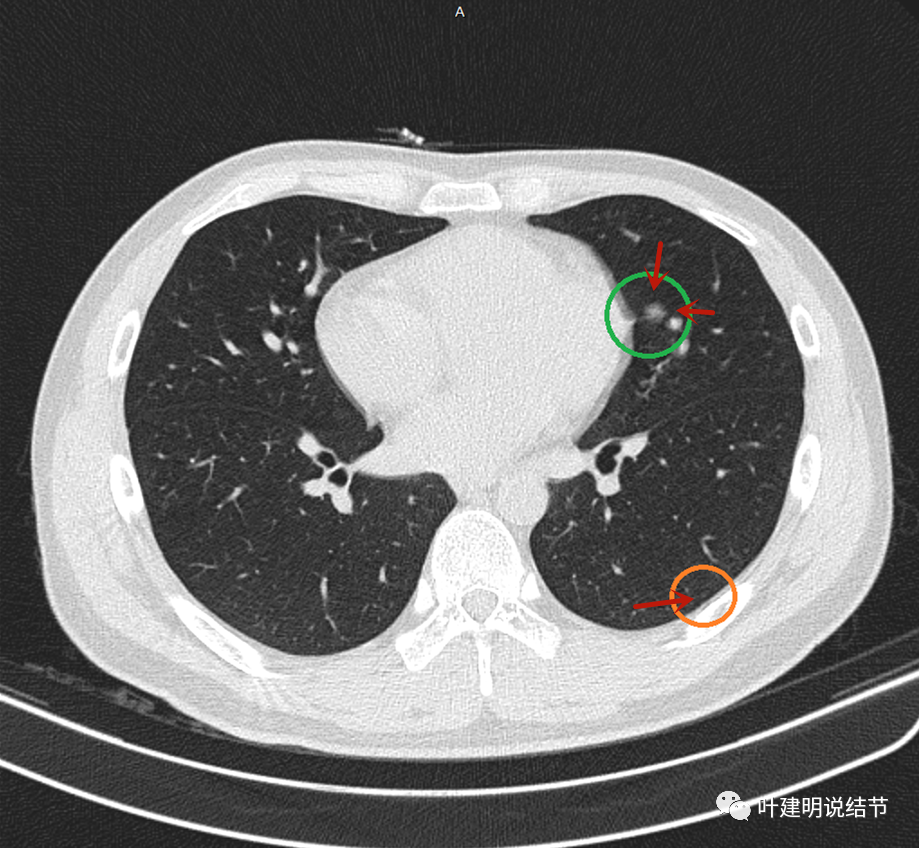

右肺上叶另见伴有小空泡的淡而微小磨玻璃结节,见蓝色圈起来的地方